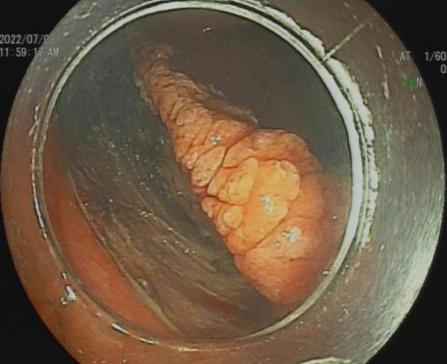

3.早期消化道肿瘤ESD技术

内镜下粘膜剥离术(ESD),具有超级微创、安全性高、住院时间短及费用低等优势,治疗早期胃癌、食管癌、大肠癌等病变,5年生存率超90%。

直肠巨大绒毛状腺瘤 内镜下粘膜剥离过程

粘膜剥离术后创面 剥离的巨大腺瘤